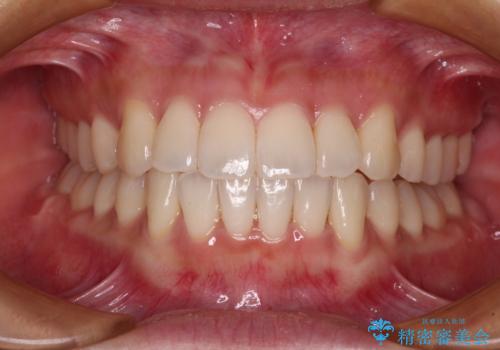

捻れた前歯をできるだけ短期間で 表側のワイヤー矯正

日々前歯の捻れが解消されていくので、歯の動きを楽しみながら矯正治療を進めることができました。